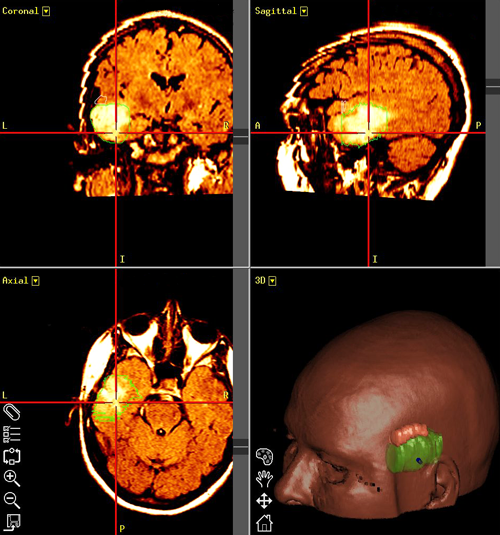

• Η Εξαίρεση Όγκου Εγκεφάλου με Κρανιοτομία με την βοήθεια Νευροπλοήγησης, Διεγχειρητικής Νευροπαρακολούθησης όπως επίσης και η Επέμβαση σε Μη Αναισθητοποιημένο Ασθενή